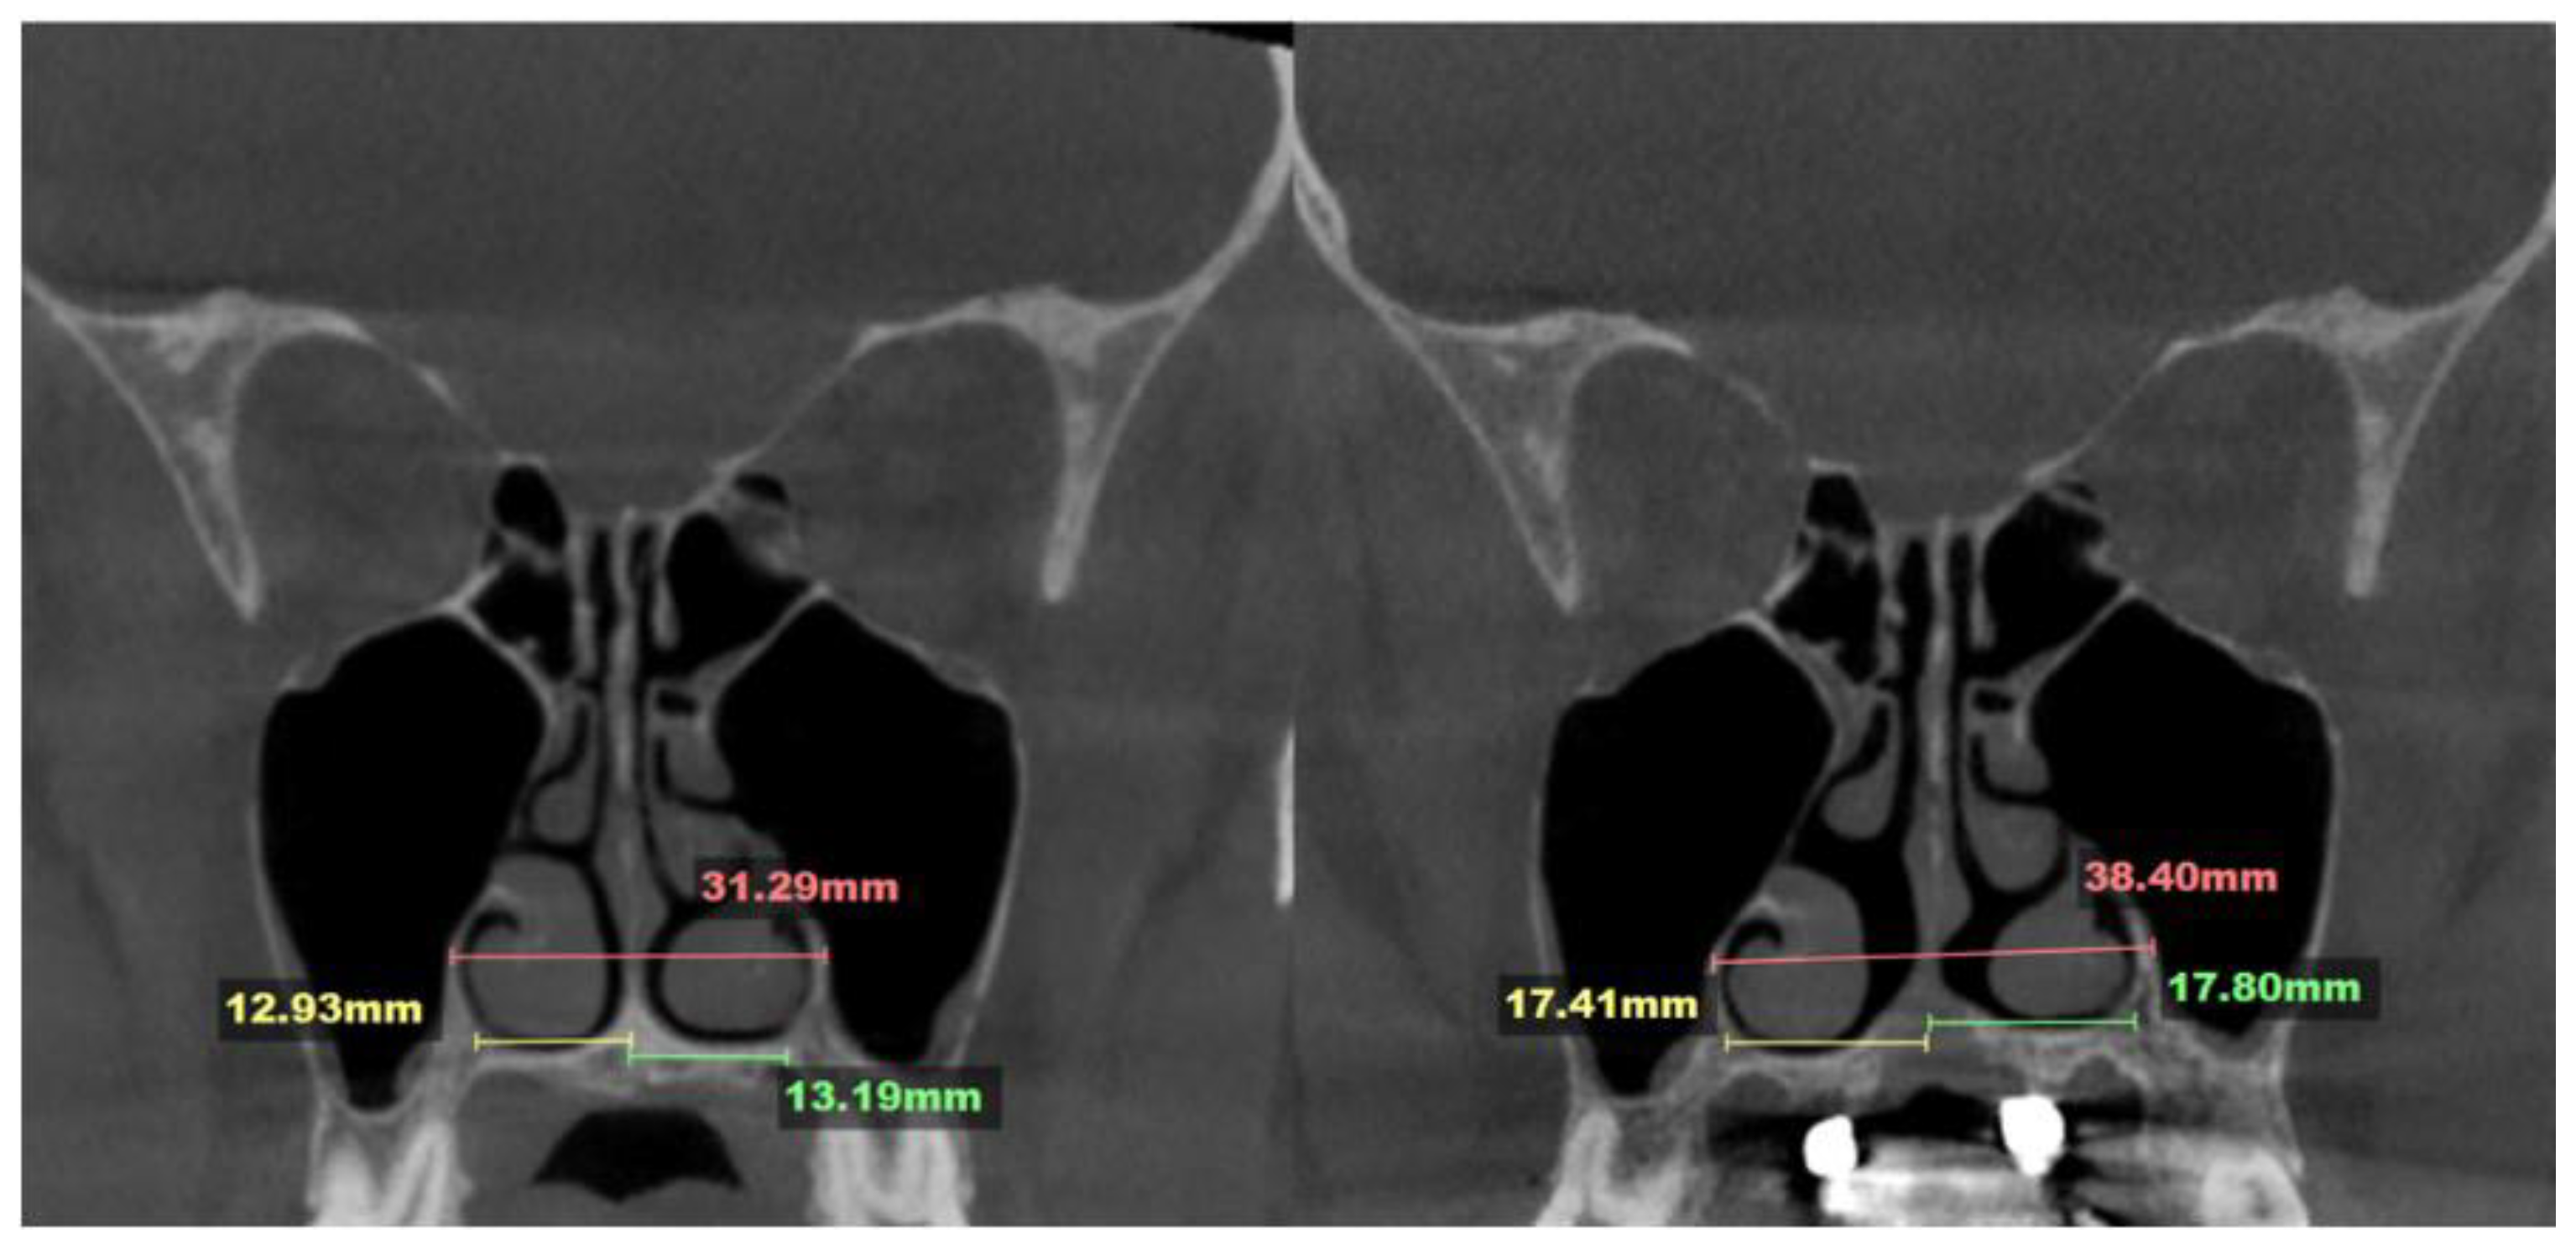

2.7. Case D: Midfacial Asymmetry Correction with Guided Expansion

- Asymmetric expansion with residual attachment of the nasal septum unilaterally to the maxillary crestal bone (Figure 5,6);

- Diagonal fractures of the palatine bone extending from the distal margin of the palatal process of the maxillary bone unilaterally, often associated with pain and tension;

- Asymmetric displacement of the nasal base floor with unilateral downward and outward movement (Figure 5,6)

- Downward inclination and displacement of the alveolar process on the ipsilateral side (Figure 5,6);

- Unilateral soft tissue shift, including nasal ala and corner of the mouth displacement toward the side of unattached separation.